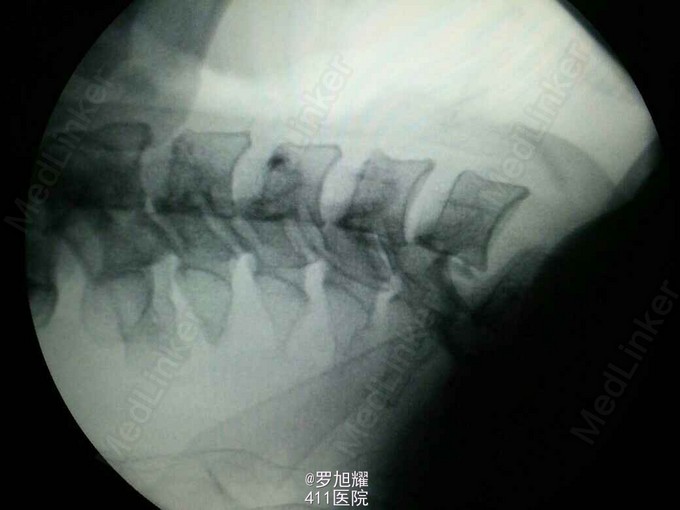

诊断:颈6/7骨折脱位伴高位截瘫。处理:立即甲强龙冲击、脱水、保胃、营养神经治疗。首选治疗方案是颅骨牵引复位后前路融合固定,较后路稳定,出血也少,和家属谈话后开始颅骨牵引复位,4kg起步,每半小时增加1kg直至14kg,调整颈椎屈伸位,再加用手法牵引仍不能复位。改用备选方案,急诊行后路切开减压撬拨复位内固定,术后瘫痪症状部分改善。随访3月双上肢前臂及手部感觉恢复,仅双手掌尺侧及小指感觉障碍,双侧三角肌、肱二三头肌肌力4-5级,腕关节屈伸、旋转肌力左侧3级,右侧3-4级,但各指肌力仍0级。

这里主要想讨论一下颈椎脱位闭合牵引复位的问题。 Mahale 等指出 , 下颈椎小关节突脱位复位后, 神经功能并发症最多见于手术切开复位 , 全麻下手法复位次之 , 颅骨牵引闭合复位最低 。作者认为, 切开复位最容易造成脊髓的直接损伤 , 而颅骨 牵引闭合复位所致脊髓功能恶化 , 主要是由于牵引方向不当, 从而加重了脊髓受压。此外 , 不论采取 何种方法复位 , 复位后脊髓水肿均是加重脊髓功能恶化的因素。 国内新桥医院骨科任先军等大重量颅骨牵引复位下颈椎小关节突脱位64例,成功60例,1例不全瘫患者复位后出现一过性左上肢根性痛加重,经脱水 、 激素治疗后缓解, 考虑可能系复位时神经根受到牵拉刺激所致。1例全瘫患者于复位后 24h 因呼吸衰竭死亡 , 其确切原因尚不十分清楚 。我们考虑可能与复位本身无直接相关 , 可能与复位后脊髓上行性水肿有关。 4 例未成功者中, 一例系呼吸困难 , 一例系关节突骨折 , 一例为陈旧性脱位 , 一例因不能耐受大重量颅骨牵引而终止复位。我们的结果表明 , 透视下大重量颅骨牵引复位是一种安全有效的方法 。 复位牵引重量平均为 27.5 kg ,最高达 40.5 kg , 远大于国内文献报道。 教科书上一般10-15kg,我加到14kg,辅以手法估计也有5kg,实在担心脊髓损伤风险,还是后路切开撬拨复位了。各位老师和同仁有什么建议和技巧,恳请点拨!